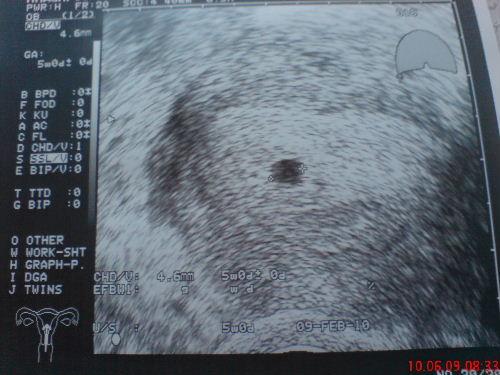

Guten Morgen! Habs gestern abend leider nimmer geschafft zu schreiben und mein erstes Ultraschallbild reinzustellen....Also, ist alles ok, Fruchthöhle war schon zu sehen und sie hat mir somit die Schwangerschaft bestätigt....Mutterpass hab ich auch schon mitbekommen und Montag muss ich wieder hin zur Blutentnahme und nochmals Ultraschall, vielleicht hab ich dann Glück und man kanns Herzchen schon schlagen sehen...So, dass war nun mein Bericht für euch....anhängend gibts natürlich noch das Bildchen von gestern. Liebe Grüsse

Bild zu So ihr Süssen... - Kinderwunsch - was tun, um schwanger zu werden?